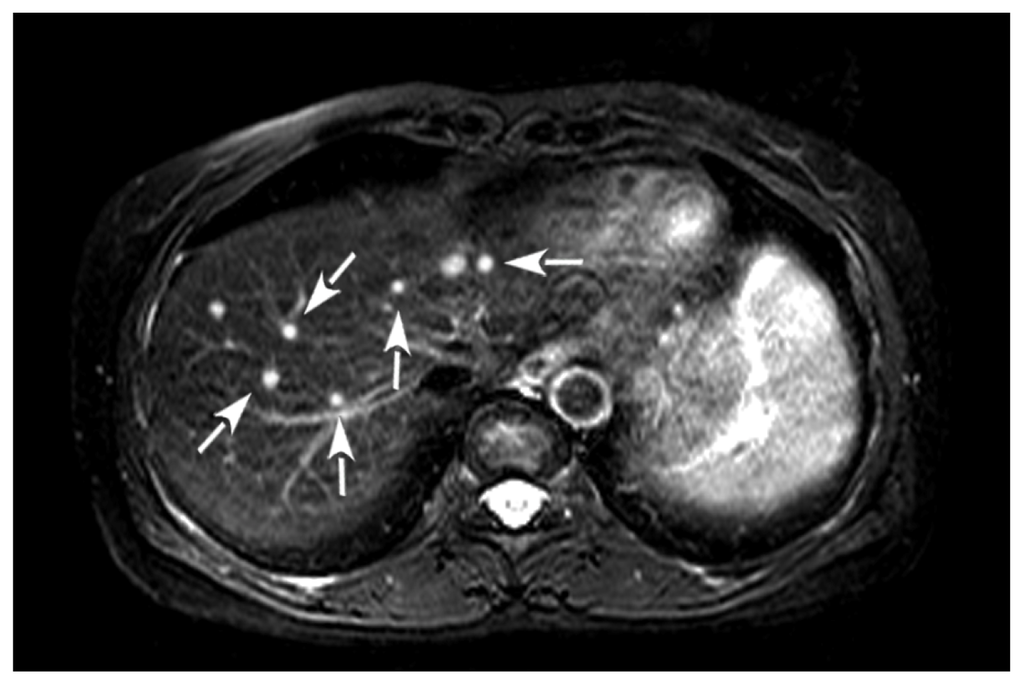

2. Case Presentation